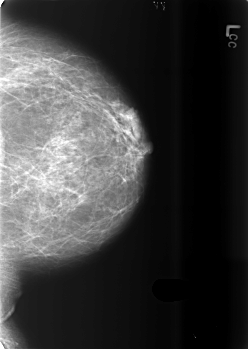

B_3432_1.LEFT_MLO

B_3432_1.LEFT_CC

LEFT_MLO LINES 5648 PIXELS_PER_LINE 3928 BITS_PER_PIXEL 12 RESOLUTION 50 NON_OVERLAY

LEFT_CC LINES 5584 PIXELS_PER_LINE 3960 BITS_PER_PIXEL 12 RESOLUTION 50 NON_OVERLAY